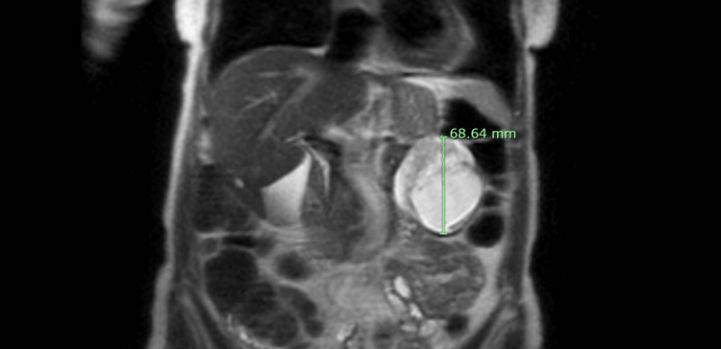

入院检查结果:体格检查无腹部压痛及其他阳性体征。实验室检查除碱性磷酸酶轻度升高(145 IU/L)外均正常。腹部及盆腔CT提示左腹部可见一约62×62×71 mm起源不明占位。腹痛自行缓解后未再发。腹部MRI进一步提示胰尾部大小约65.00×62.17×68.64 mm混合囊实性占位,呈周边强化并伴扩散受限(图1和图2)。该肿块可能起源于胰尾,考虑恶性可能,未见转移征象。

图2. MRI冠状位SS-FSE序列图像。

腹部无对比剂MRI显示复杂混合囊实性占位的另一种视图,伴周边强化及扩散受限,可能起源于胰尾的前部,但显然也与胃后壁分界不清